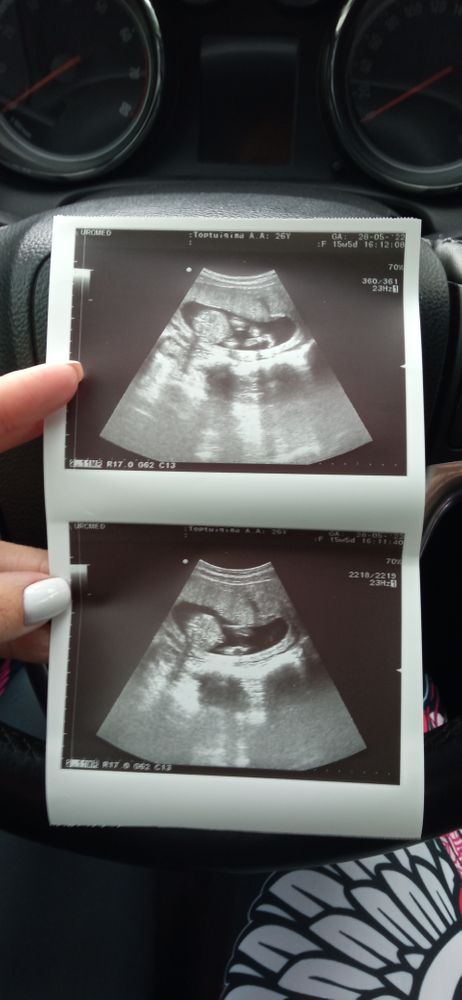

Вроде как и половые губы а вроде как и яички. Я за девочку больше

У вас похоже на девочку.

Склоняюсь сильно к девочке. Конечно ещё зависит от ракурса - либо это ракурс прямо на попу, либо на попу со спины. Но всё-таки мошонки не вижу. Ножки вроде не скрещены, не поджаты - иначе я могла бы предположить, что ножками прижали там детальки) У меня есть мой мальчик снимок 17 недель, ракурс на ягодичку. Мошонка вообще кажется очень большой, хорошо заметна даже несмотря на то, что вид частично со спины.

Это попа снизу? Что-то не могу фото разобрать 🙈

с одной стороны похоже на мошонку, но кружочек у вас розовый🤔

Раз кружочек розовый, значит, врачи увидели девочку) Вряд ли тут по фото тети из интернета увидят что-то другое. Честно говоря, по этим фото мне не очень понятно кто. Вроде и на мальчика не похоже, но и у дочки на УЗИ немного по-другому выглядело, поэтому сложно сказать🤔